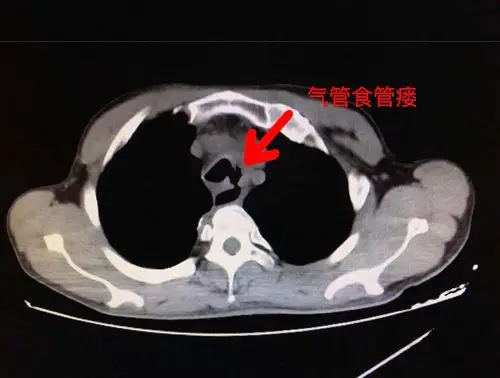

食管瘘的观察及护理

亡羊补牢,尤为未晚 —— 一例复杂气管食管瘘的成功救治_气管食管瘘

气管食管瘘 - 好大夫在线

机械通气相关的气管食管瘘.ppt

气管-食管瘘 3.

食管气管瘘,食管覆膜支架显神威——我院消化内科成功治疗食管气管瘘